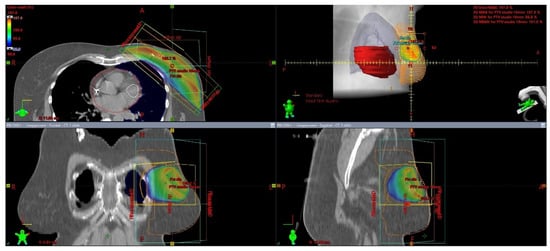

The issue of using radiotherapy in patients who have undergone immediate breast reconstruction and in whom post-mastectomy radiation therapy (PMRT) is indicated remains controversial. Available data indicate that a majority of patients undergoing immediate reconstruction have an implant placed during the surgery [58]. Figure 3 presents an isodose plan for a patient with an inserted silicone implant.

Figure 3.

Breast irradiation after radical mastectomy with silicone implant insertion. A dose greater than 90% of the prescribed dose is displayed in color. The maximum dose in this slice is 105.6 % of the prescribed dose.